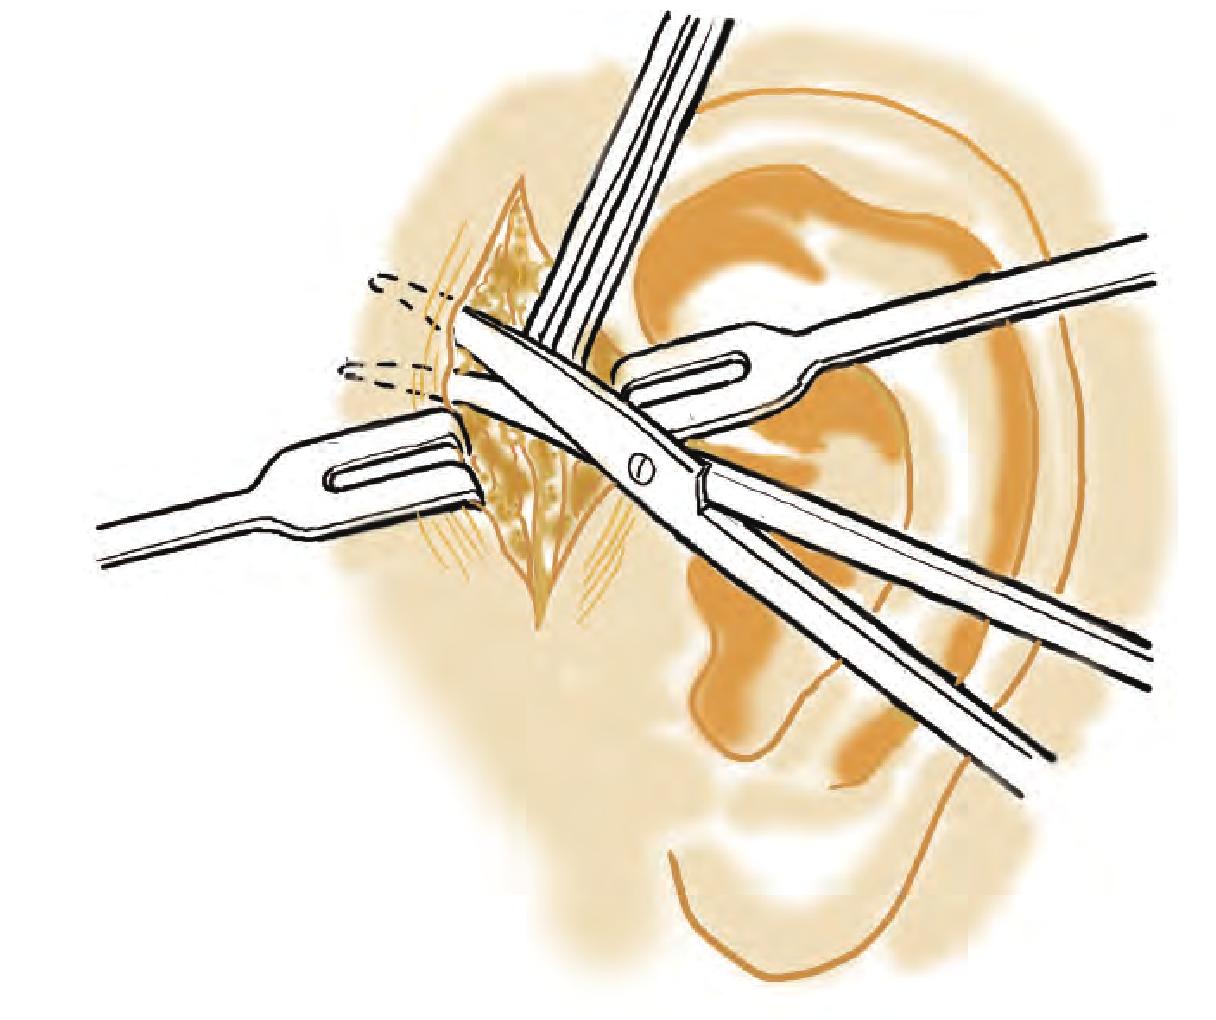

SRSS 的确切原因尚不清楚,但可能涉及以下因素:神经损伤: 手术可能会损伤手术部位的神经,导致异常的感觉。炎症: 手术部位的炎症可能会刺激神经。疤痕组织: 手术后的疤痕组织可能会压迫或拉扯神经。异物: 手术部位的异物,如缝线或手术器材,可能会刺激神经。